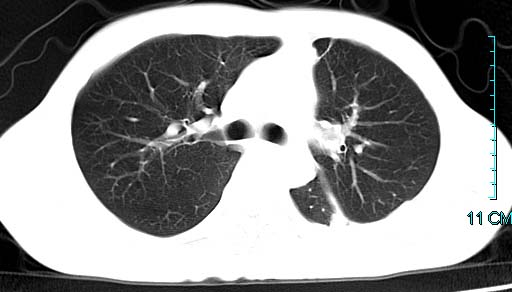

以下是引用qian在2006-3-28 14:32:00的发言:[br]左肺下叶大片状阴影,密度不均,见有条片影和空洞及气液平,少量胸腔积液伴有胸膜增厚,从图像看积液密度比水的密度高,结合病史,考虑左下肺化脓性炎症伴有脓胸。

以下是引用wawaquan在2006-3-28 22:25:00的发言:[br]左上肺舌段多发斑片影。结合“男24y咳嗽咳痰气促伴高热(38.5--39.5)20多天”及穿刺史,[br]考虑1 左下肺化脓性炎症;2脓胸。

以下是引用乡医在2006-3-28 18:37:00的发言:[br]左侧多发液气平面结合患者男24y咳嗽咳痰气促伴高热(38.5--39.5)20多天,查胸水:ldh239.3,总蛋白59.19,tb-ab阴性,利凡它试验+,红c2.7*109,白c1.08*109,分类淋巴92%分叶8%,考虑1脓胸2肺隔离征感染